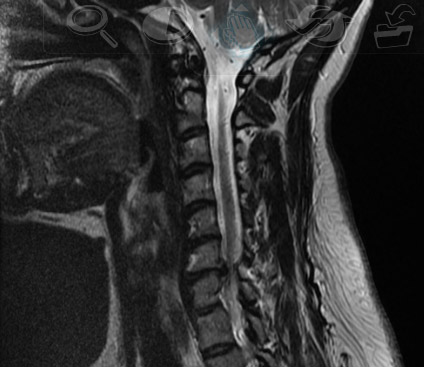

ESTA CONDICION PRODUCE DOLOR EN LA COLUMNA Y PUEDE PRESENTARSE A NIVEL DEL CUELLO O REGION CERVICAL O A NIVEL DE LA COLUMNA LUMBAR FRECUENTEMENTE SE ACOMPAÑA DE DIFICULTAD PARA CAMINAR QUE HACE QUE LAS PERSONAS NO PUEDAN CAMINAR DISTANCIAS CORTAS O METROS Y TENGAN QUE PARAR POR QUE EL DOLOR EN LAS PIENAS Y EL DOLOR SE VUELVE TAN INTENSO Y TENGAN QUE DESCANSAR Y SENTARSE EN LA CALLE UNOS MINUTOS PARA RETOMAR LA MARCHA EL DIAGNOSTICO ES CLINICO Y SE DEBE HACER UNA RESONANCIA MAGNETICA . Tal vez usted es una de esas personas que tiene problemas para caminar o tal vez su problema son dolores de cabeza ALTERACIONES DE LA SENSIBILISAS Y FUERZAS de los brazos o debilidad muscular. Hay muchas maneras en las que se puede sentir la estenosis espinal.

EL DIANOSTICO ES MEDICO Y DEBE HACERASE UNA RESONANCIA MAGNETICA PARA EVALUAR EL GRADO DE ESTRECHAMIENTO EL TRATAMIENTO INICIAL ES MEDICO Y EN ALGUNOS CASOS SE BENEFICIAN CON LOS BLOQUEOS O INFILTRACIONES SI NA HAY MEJORIA HAY QUE CONSIDERAR LA CIRUGIA